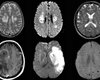

Новое исследование показало, как коронавирус влияет на головной мозг